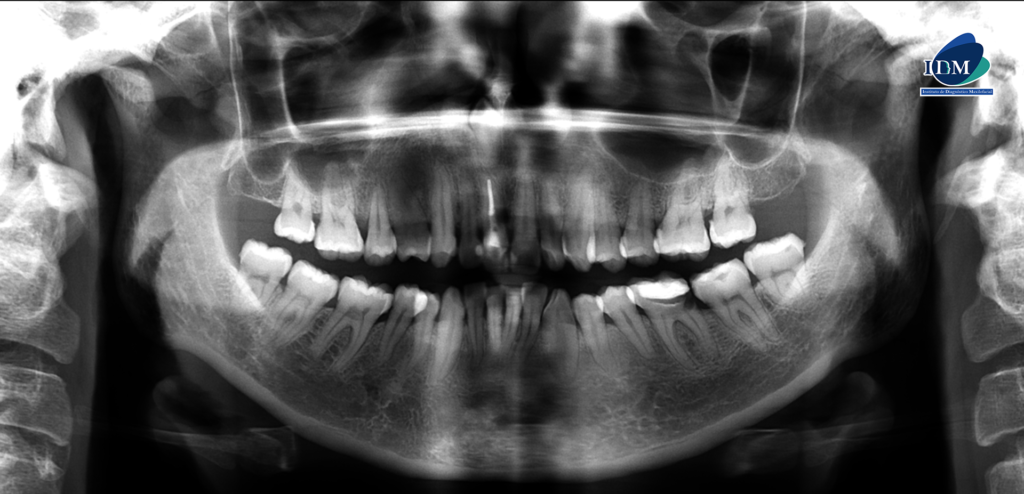

A la evaluación de la radiografía panorámica se evidencia un diente supernumerario retenido en posición invertida en sector anterosuperior.

Radiografia Panorámica

Así mismo en la tomografía volumétrica de haz se evidencia que dicha pieza está ubicada en zona vestibular. Contactando con el conducto nasopalatino, próximo a ápice de la pieza 11 y con el segmento coronario contactando con piso de fosa nasal derecho.

Conclusión imagenológica:

- Mesiodens retenido